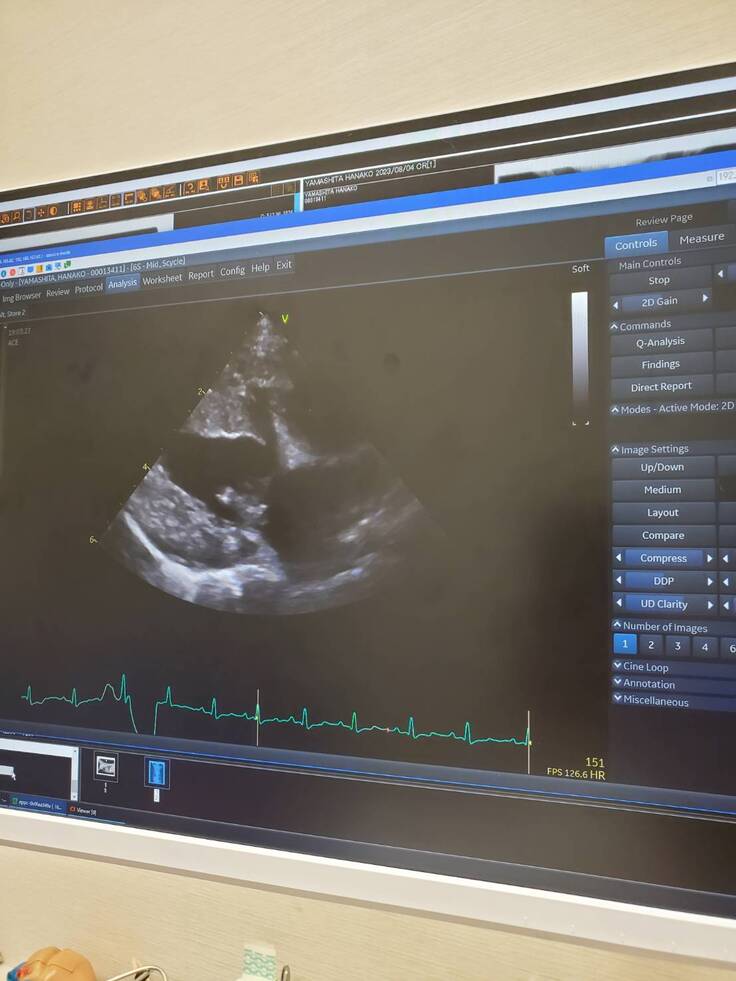

術後1か月検診

先週、術後1か月検診に行ってきました

逆流はほぼなく、術前より心臓が小さくなってました😊

血液検査も異常はなし